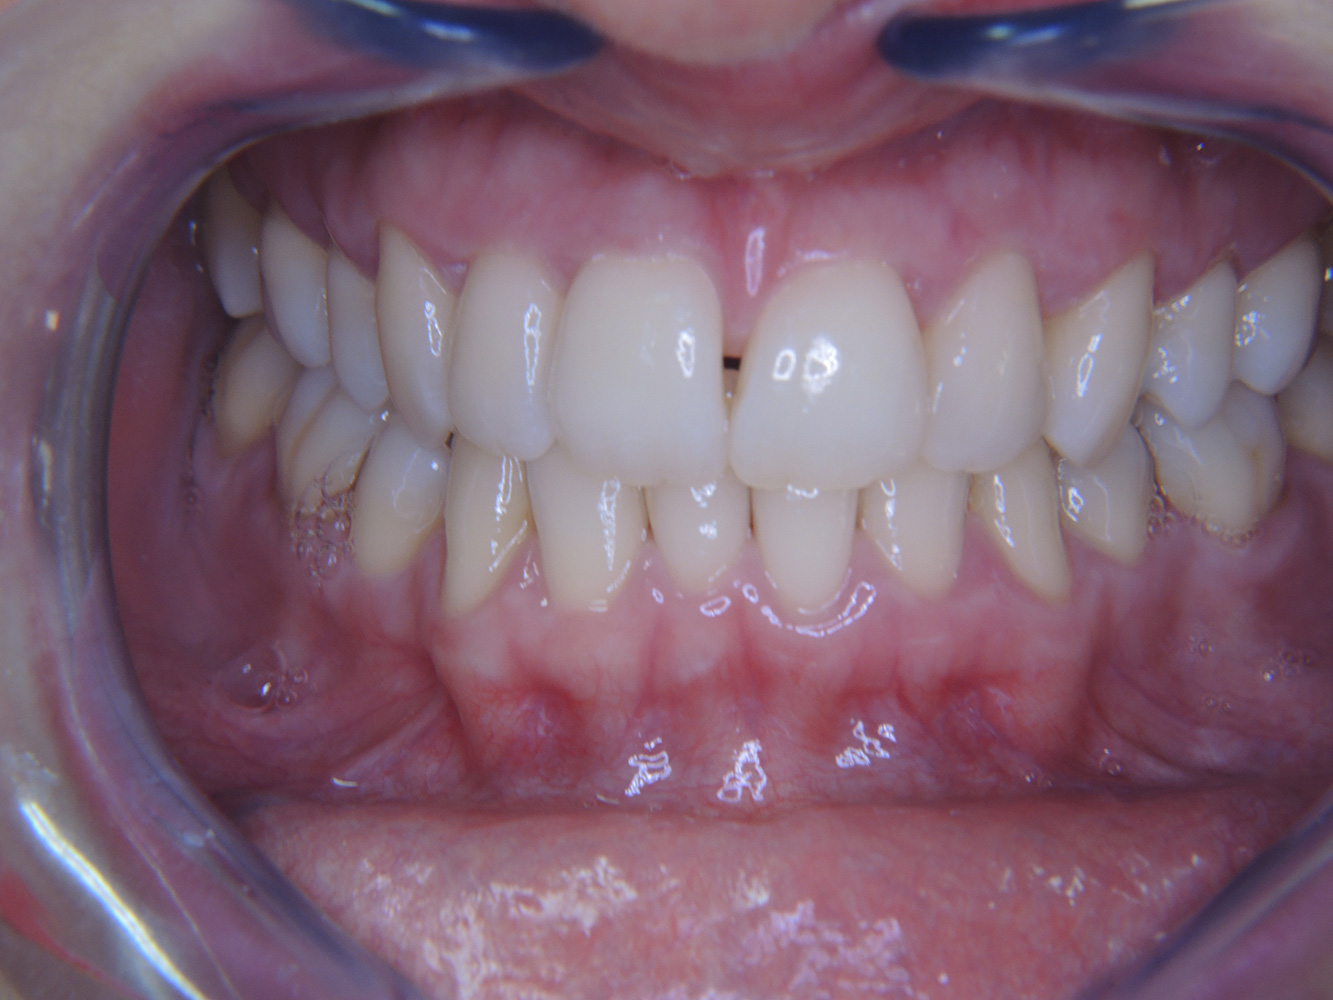

Eine 51-jährige mundgesunde Diabetikerin stellt sich zur Präventionssitzung vor. Die Blutzuckerwerte sind stabil bei einem HbA1c = 6,2%, folglich gilt sie mit dem entsprechenden Medikament Metformin (Antidiabetikum) als suffizient eingestellt. Die Patientin hat keine bestehenden Versorgungen oder orale Vorerkrankungen. Anhand der aktuellen Befunde lässt sich eine Gingivitis bei sonst stabilem parodontalem Zustand (Stage II, Grad B) feststellen. mehr Infos